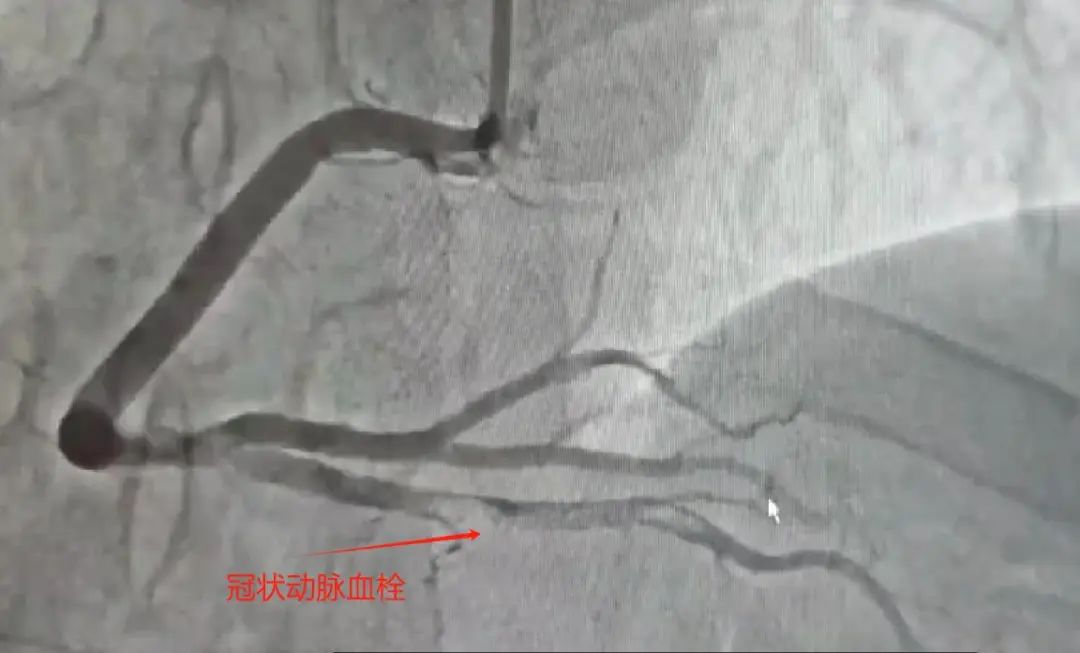

术中所见:右冠状动脉粗大,远段狭窄60-70%,后降支开口近段毛玻璃状大血栓,果断为患者实施了血栓抽吸术,抽出新鲜红色血栓,考虑患者年纪轻,右冠状动脉远段病变临界,本着无植入原则,使用药物球囊充分扩张病变,复查造影无残留血栓,治疗效果满意。